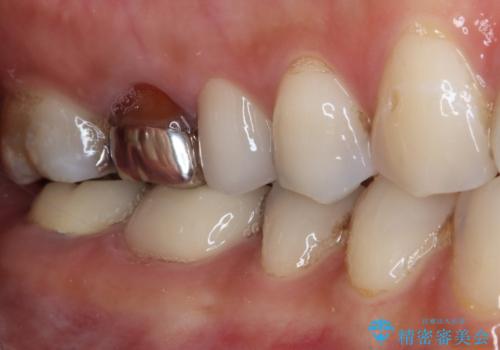

神経が除去されている歯、根管治療の必要な歯、むし歯の非常に大きな歯に対してオールセラミッククラウンにて補綴治療を行うこととしました。

左上の欠損部はインプラントを埋入した上で補綴することとしました。